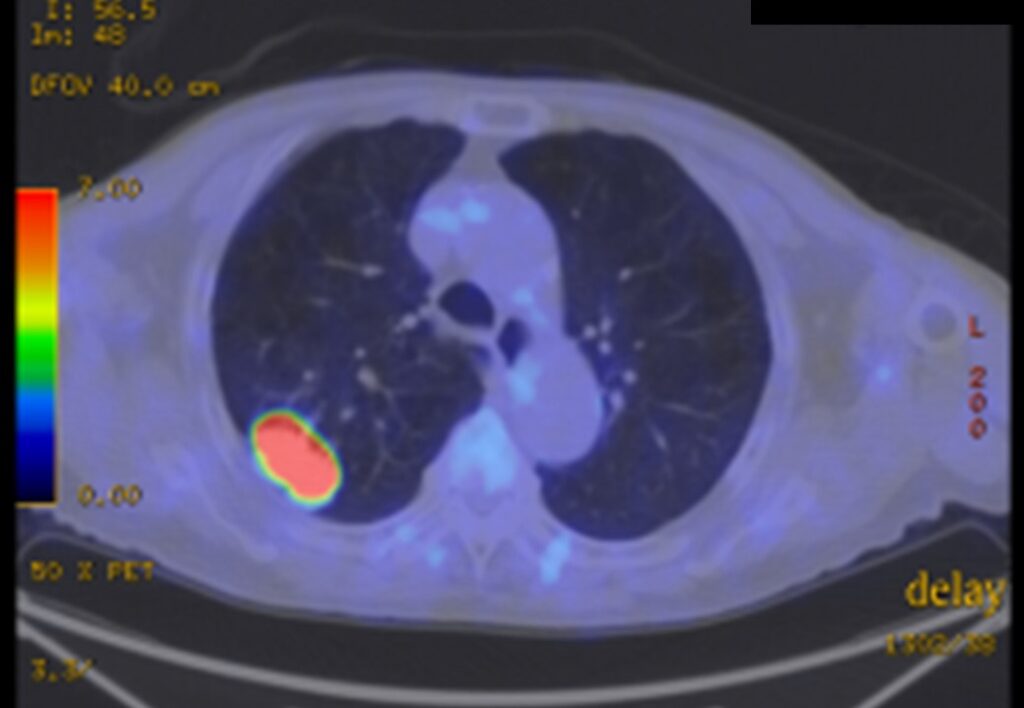

開院以来、肺癌手術の95%が胸腔鏡を使用して行われています。もっとも多い術式は胸腔鏡下肺区域切除術です。また気管支形成術や血管形成術などの難しい手技が必要な場合でも胸腔鏡による手術が行われています。当科ではCT画像を基に術前に肺動静脈や気管支の立体画像を作成して、手術方法の検討や手術のシミュレーション、術中ナビゲーションに活用し、安全確実に手術を行うように努めています。